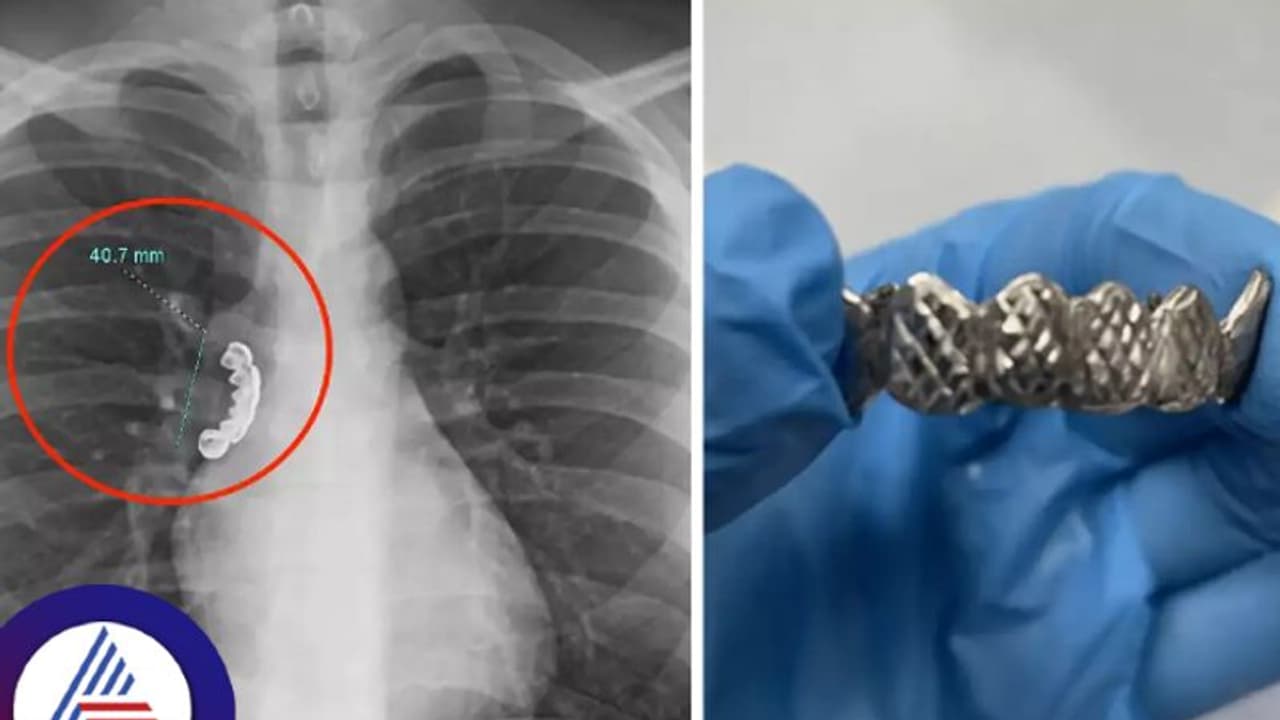

ನಂಬೋಕೆ ಕಷ್ಟವಾದರೂ ಇದು ನಿಜ. 22 ವರ್ಷದ ವ್ಯಕ್ತಿ, ಆಕಸ್ಮಿಕವಾಗಿ ದಂತಗಳನ್ನು ನುಂಗಿದ್ದು, ನಂತರ ಇದು ಶ್ವಾಸಕೋಶದಲ್ಲಿ ಸಿಲುಕಿ ಹಾಕಿಕೊಂಡಿದೆ. ವಿಸ್ಕಾನ್ಸಿನ್ನ ವ್ಯಕ್ತಿಯೊಬ್ಬ ಬೆಳ್ಳಿಯ ನಕಲಿ ಹಲ್ಲಿನ ಸೆಟ್ನ್ನು ದರಿಸಿದ್ದಾನೆ. ಆದರೆ ಆಹಾರ ಸೇವಿಸುವಾಗ ಆಕಸ್ಮಿಕವಾಗಿ ಹಲ್ಲಿನ ಸೆಟ್ನ್ನು ನುಂಗಿಬಿಟ್ಟಿದ್ದಾನೆ. ಇದರ ಪರಿಣಾಮವಾಗಿ ವ್ಯಕ್ತಿಯಲ್ಲಿ ಭಾರೀ ಕೆಮ್ಮು ಮತ್ತು ಉಬ್ಬಸ ಕಾಣಿಸಿಕೊಂಡಿತು.

ಶ್ವಾಸನಾಳದಲ್ಲಿತ್ತು 1.5 ಇಂಚಿನ ಹಲ್ಲಿನ ಸೆಟ್

ಕ್ಯುರಸ್ ವೈದ್ಯಕೀಯ ಜರ್ನಲ್ನಲ್ಲಿ ಈ ವಾರ ಪ್ರಕಟವಾದ ಕೇಸ್ ಸ್ಟಡಿ ಪ್ರಕಾರ, ವ್ಯಕ್ತಿಯನ್ನು ಆಸ್ಪತ್ರೆಗೆ (Hospital) ಕರೆದೊಯ್ದು ಎಕ್ಸ್ರೇ ತೆಗೆಯಲಾಯಿತು. ಈ ಸಂದರ್ಭದಲ್ಲಿ ಅವರ ಶ್ವಾಸನಾಳದಲ್ಲಿ (Lungs) 1.5 ಇಂಚಿನ ಹಲ್ಲಿನ ಸೆಟ್ ಸಿಲುಕಿಕೊಂಡಿರೋದು ತಿಳಿದುಬಂತು. ನಂತರ ವೈದ್ಯರು ಬ್ರೋನೋಸ್ಕೋಪಿ ಮಾಡಿ ಶ್ವಾಸನಾಳದಲ್ಲಿ ಸಿಲುಕಿದ್ದ ಹಲ್ಲಿನ ಸೆಟ್ನ್ನು ಹೊರತೆಗೆದರು. ಬ್ರೋನೋಸ್ಕೋಪಿ ಎಂಬುದು ಶ್ವಾಸಕೋಶಕ್ಕೆ ಫ್ಲೆಕ್ಸಿಬಲ್ ಟ್ಯೂಬ್, ಬ್ರೋನೋಸ್ಕೋಪ್ನ್ನು ಬಳಸಿ ಸಿಲುಕಿಹಾಕಿಕೊಂಡಿರುವ ವಸ್ತುವನ್ನು ಹೊರತೆಗೆಯುವ ವಿಧಾನವಾಗಿದೆ.

ಈ ಚಿಕಿತ್ಸೆಯಿದ ಶ್ವಾಸಕೋಶದ ಸ್ನಾಯುಗಳು ಬಿಗಿಯಾದ ಅನುಭವವಾಯಿತು ಎಂದು ರೋಗಿ (Patient) ತಿಳಿಸಿದ್ದಾನೆ. ನಂತರ ವೈದ್ಯರು ಸ್ಟೀರಾಯ್ಡ್ ಚಿಕಿತ್ಸೆಯನ್ನು (Treatment) ನೀಡಿದರು. ಬಳಿಕ ವ್ಯಕ್ತಿಯನ್ನು ಆಸ್ಪತ್ರೆಯಿಂದ ಡಿಸ್ಚಾರ್ಜ್ ಮಾಡಲಾಯಿತು. ವ್ಯಕ್ತಿ ನಿರಂತರವಾಗಿ ಸ್ಟೀರಾಯ್ಡ್ ಚಿಕಿತ್ಸೆ ತೆಗೆದುಕೊಳ್ಳಲು ಸೂಚನೆ ನೀಡಲಾಗಿದೆ ಎಂದು ತಿಳಿದುಬಂದಿದೆ.